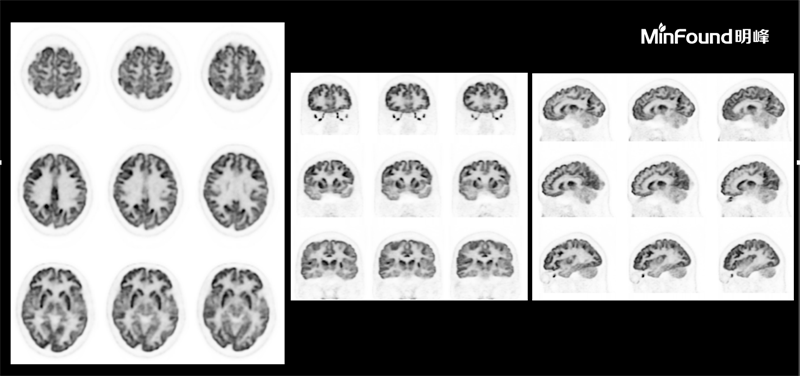

ScintCare PET/CT 730T

ScintCare PET/CT 730T employs a 4th-generation PET detector where lutetium-yttrium oxyorthosilicate (LYSO) crystals are individually coupled to SiPM detectors without the optical conductor (1: 1 coupling and 100% coverage). The digital SiPM detector considerably minimizes photon loss, resulting in improved time resolution (380 ps), system sensitivity (23.5 cps / kBq), and image uniformity, ultimately resulting in high-resolution images under well-curated radiation dose control.

ScintCare PET/CT 730T axial FOV reaches 40.3 cm width, enabling the whole-organ scan just by one-bed position and the whole-body scan by two-bed positions in about 3 minutes time. The ultra-fast data acquisition greatly supports the large patient throughput.